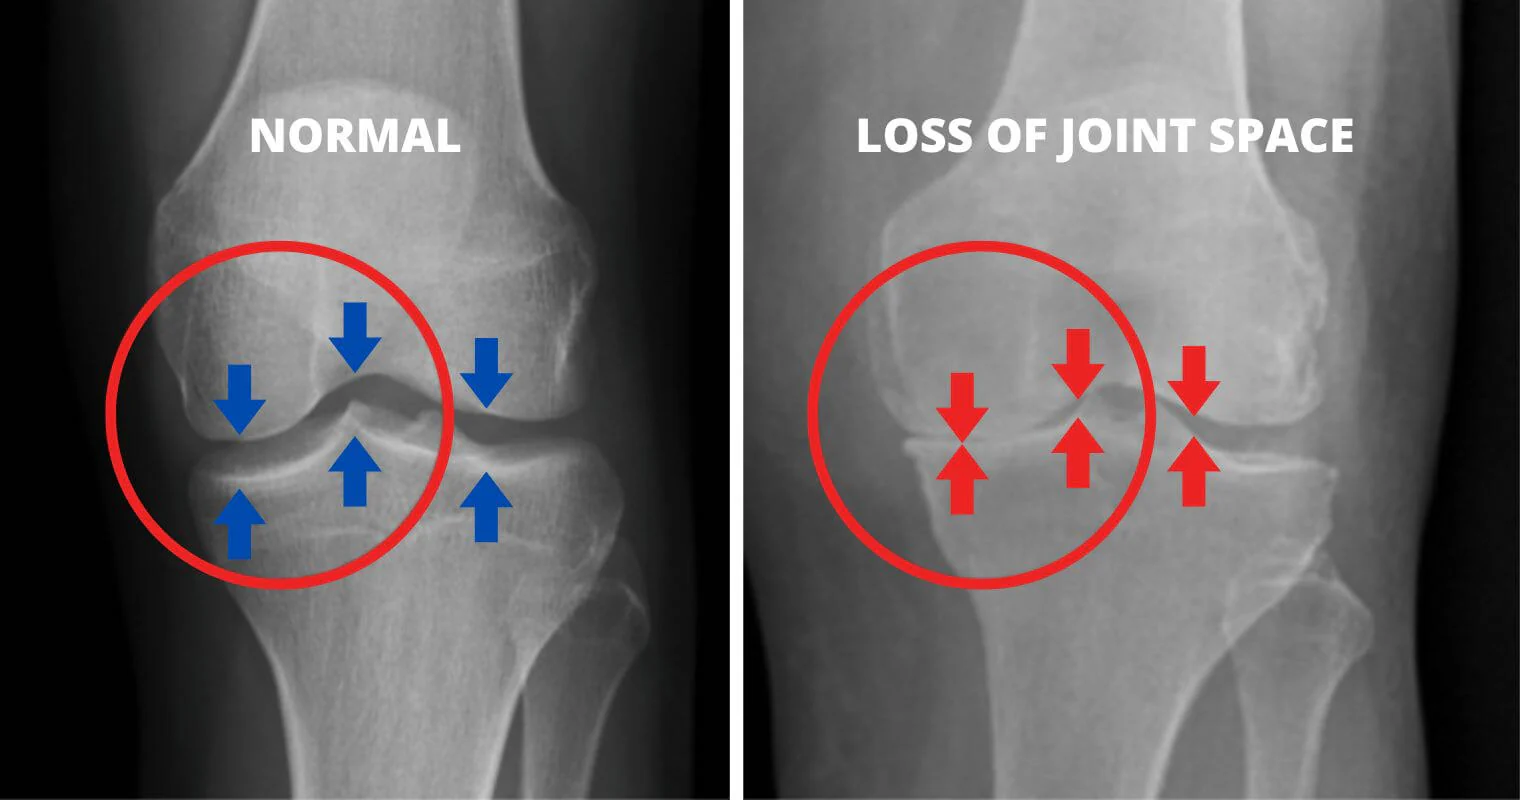

What if I told you that the knee pain and stiffness you feel are caused by the wear and tear of your cartilage, leading to uncomfortable friction?

As the cartilage wears away over time, the bones start to rub against each other, causing intense pain and discomfort.This friction leads to discomfort, swelling, and a significant reduction in mobility.

As you age and continue toput stress on your knees, the cartilage deteriorates.And when this happens, you start experiencing severe pain due to the bones rubbing together.